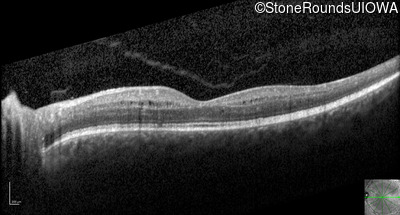

Optical Coherence Tomography - Right - 20/25 -1

Exemplar / OCT Stack